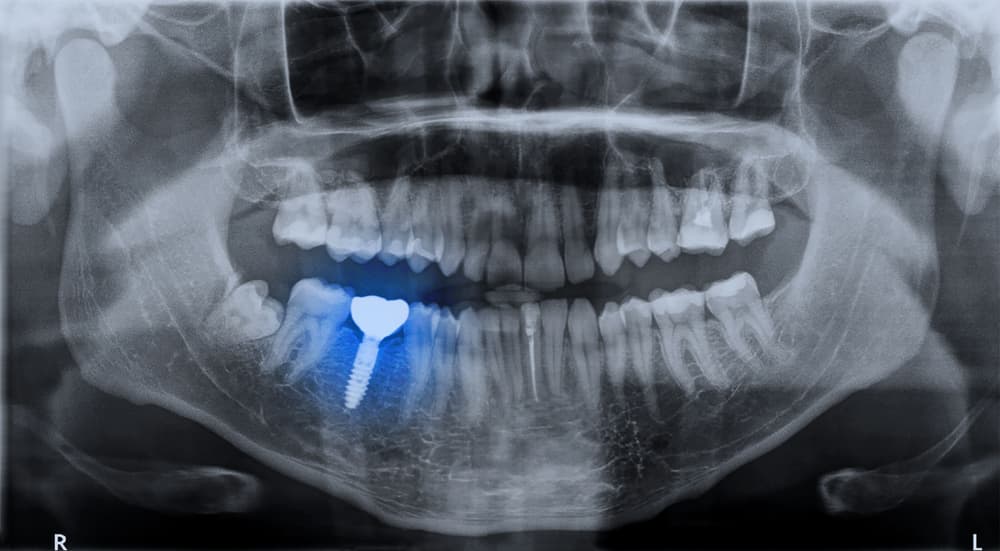

Dental implants are small titanium or zirconia posts surgically placed into the jawbone to act as artificial roots. Over several weeks, the implant undergoes osseointegration, where living bone cells attach firmly to the implant surface. Once healed, the implant can support a crown, bridge, or denture with remarkable stability.

Because implants directly stimulate the alveolar bone, they prevent the resorption process and preserve facial contours. Implants are also bioinert, meaning the body does not reject them, and modern surface treatments (such as sandblasting and acid-etching) enhance bone bonding for long-term success.